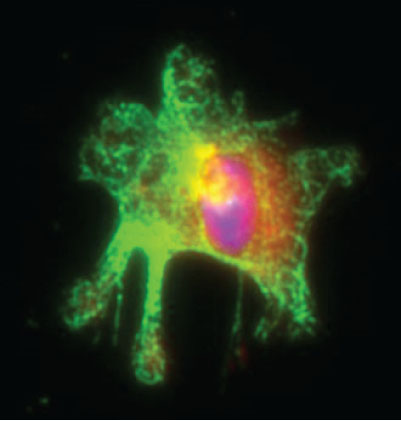

A new study by researchers at IRB Barcelona demonstrates that myeloid cells, which belong to the leucocyte family and form part of the innate immune system, use p38 protein signalling to support inflammation-associated colon cancer.

Scientists headed by ICREA researcher Angel R. Nebreda at the Institute for Research in Biomedicine (IRB Barcelona) report a new mechanism that contributes to the development of inflammation-associated colon cancer and points to new therapeutic targets. The study has been published in the journal EMBO Molecular Medicine.